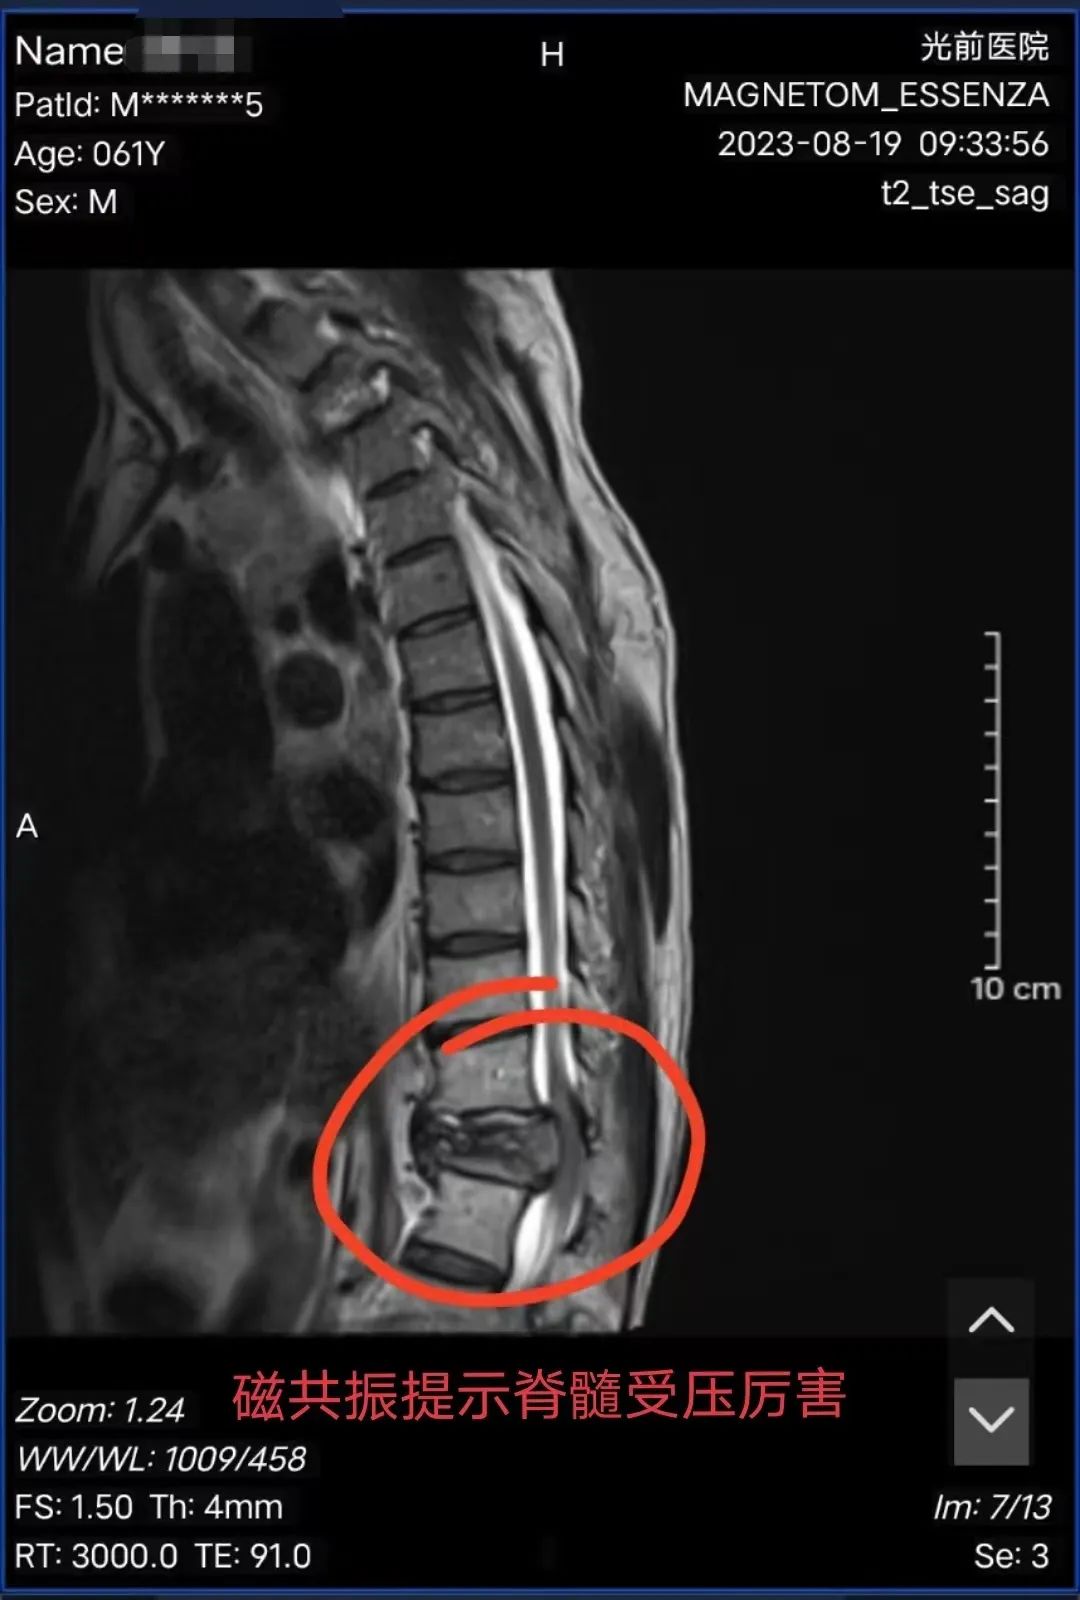

患者陳阿伯,永春人,以“確診右肺癌1年并治療后,腰痛伴左下肢乏力2天”為主訴入住我院腫瘤放療三區(qū),入院后完善MRI提示“胸12椎體病理性骨折并椎管狹窄,脊髓損傷”,經(jīng)骨科詹志強(qiáng)主治醫(yī)師會(huì)診后,考慮陳阿伯為急性胸12椎體病理性骨折并不全癱瘓,且癱瘓程度呈進(jìn)行性加劇趨勢。既往已有轉(zhuǎn)移病灶放療病史,再次給予保守治療,效果不佳,脊柱穩(wěn)定會(huì)繼續(xù)加重,陳阿伯將面臨完全癱瘓的困境,與陳阿伯及家屬溝通后,告知符合手術(shù)指征,陳阿伯及家屬表示相信我院骨科技術(shù)水平,決定手術(shù)治療。

▲手術(shù)前后影像對比